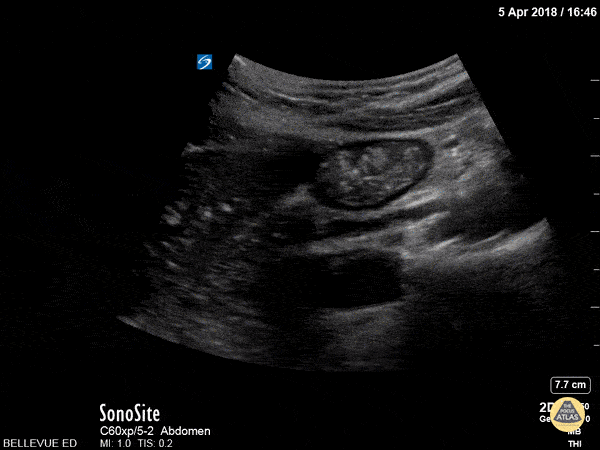

In this clip the probe is positioned over the RUQ. The liver is on the left side of the screen, and in the center of the screen we see a portion of the duodenum in cross-section. Often mistaken for a gallbladder full of gallstones by novices sonographers, it can be identified by its peristaltic waves with visible motion of the bowel contents within. Hannah Kopinksi and Dr. Lindsay Davis - NYU Emergency Medicine